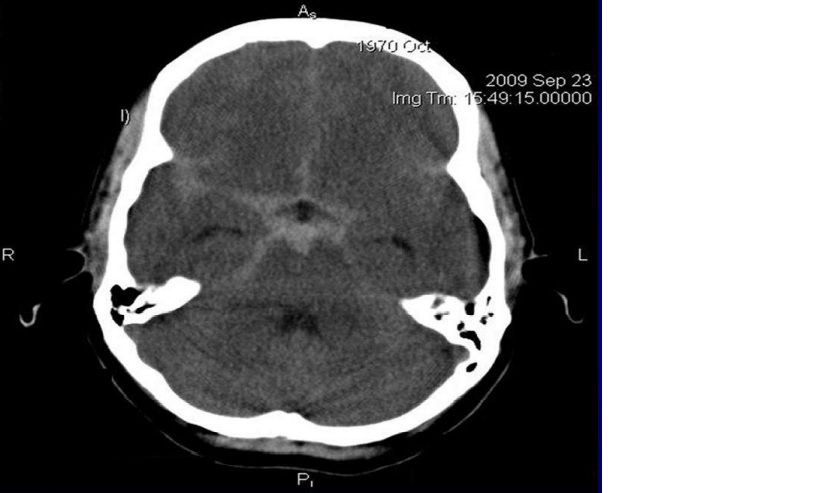

CT đầu không cản quang : bình thường

BN được chỉ định DSA

CTA

Chẩn đoán hình ảnh: 3 túi phình động mạch cảnh trong bên (P) đoạn quanh động mạch mắt.Túi phình 1:2.4x2mm,cổ 2.4mm.Túi phình 2:2.5×2.4mm,cổ 2.2mm.Túi phình 3:3.7x3mm,cổ 3mm. -2 túi phình động mạch cảnh trong bên (T) đoạn quanh động mạch mắt.Túi phĩnh 4:3.4×3.7 mm,cổ 3.4mm.Túi phình 5:3.7×4.3 mm,cổ 3.7 mm. -1 túi phình động mạch đỉnh thân nền : 4×3.7×4.3mm,cổ 3.7 mm.

Chẩn đoán xác định: Xuất huyết dưới nhện do vỡ đa túi phình mạch não